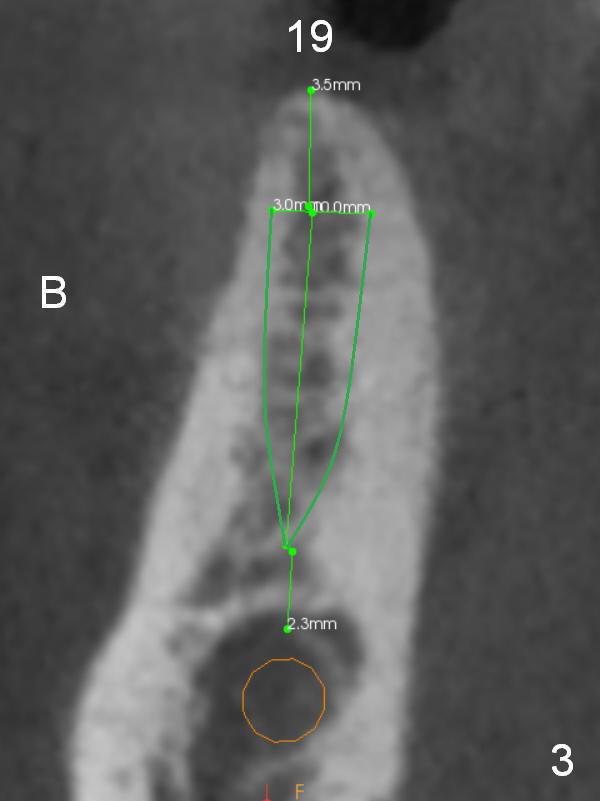

A 71-year-old man requests restoration at #18-20 (Fig.1). Placing implants at the narrow ridge of the sites of #18 and 19 is quite challenging (Fig.3,4), as compared that at #31 (Fig.5). Since the bone density at the crest is high (1200-1500 u), use a surgical high speed fissure bur for sectioning the crest, followed by BEB at 11 mm. It appears safer to place 1-piece implant (Fig.3) than 2-piece one (Fig.4). Since the total mesiodistal distance for #18-20 is 18 mm, splinting the three-units should be a sound treatment option.